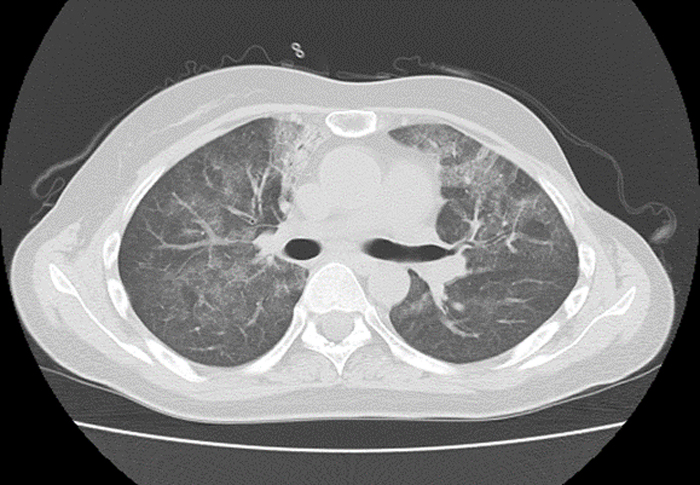

抹消がスペアされたすりガラス陰影はニューモシスチス肺炎に典型的、ですが 上肺野の画像を出さないのはちょっと意地悪かなぁと思ってしまいます。 この状態だとサイトメガロ感染症は 合併 していてもおかしくはありませんが、最も考えられるのはニューモシスチス肺炎 1 2 診断のアプローチ 治 療 ⑴ どのようなときに疑うか 体動時の息切れ、咳嗽、発熱、呼吸困難が出現したとき。胸部x線写真の陰影が出現する 以前に、肺拡散能や動脈血酸素分圧が低下することもある。5肺・胸膜 (10)ニュウモシスティス肺炎病理コア画像 5肺・胸膜 (10)ニュウモシスティス肺炎 ミクロ像(HE弱拡大):TBLBの材料。 肺胞内に好酸性(エオジンに染まる)泡沫状の滲出物を認める。 画像をクリックすると拡大表示します。

逆に、aids患者の気胸を見たときには、ニューモシスチス肺炎を疑う。 亜急性〜慢性(28週)の経過で発症。一方でnonhivは急性。 aids患者の60%がpcp発症で発見。 nonhivpcpは死亡率3550%。hivpcpは死亡率10%。 症例 hiv陽性患者のpcp画像所見2症例 Kerley line,hilar haze, 気管支血管周囲肥厚 :左心不全 Tram line:気管支拡張症,気管支炎,びまん性汎細気管支炎 (画像引用元 不明) 47 ニューモシスチス肺炎のスリガラス影 48 ニューモシスチス肺炎のスリガラス影 (XPで見える場合) 49>画像所見 : 両下肺野優位で微細な網状影とすりガラス影が広がっている。 >診断 : ニューモシスチス肺炎(旧 カリニ肺炎) >解説 : 広範なすりガラス影を示す代表的な疾患としては、 ニューモシスチス肺炎とサイトメガロウイルス肺炎があげられる。

ニューモシスチス肺炎 カリニ肺炎 Pcp のct画像診断のポイント